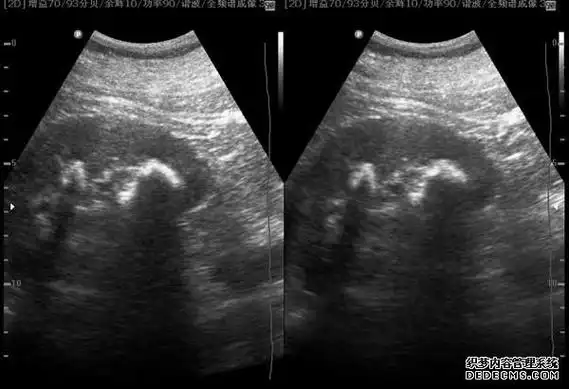

马蹄肾合并左肾结石

考虑患者疼痛显著,且已因结石梗阻产生左肾积水,为免病情加重危害肾脏